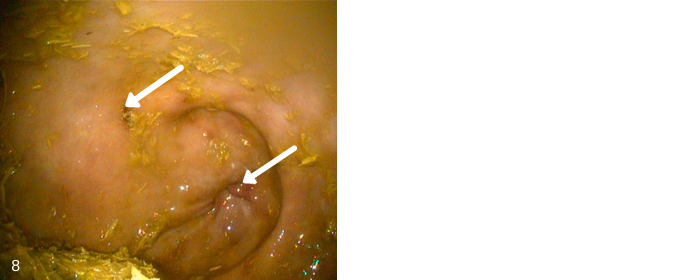

Image 8 – This picture shows several areas of moderately severe glandular ulcers at the pyloric closeding. This horse showed no weight loss however was girthy and cranky when saddled.